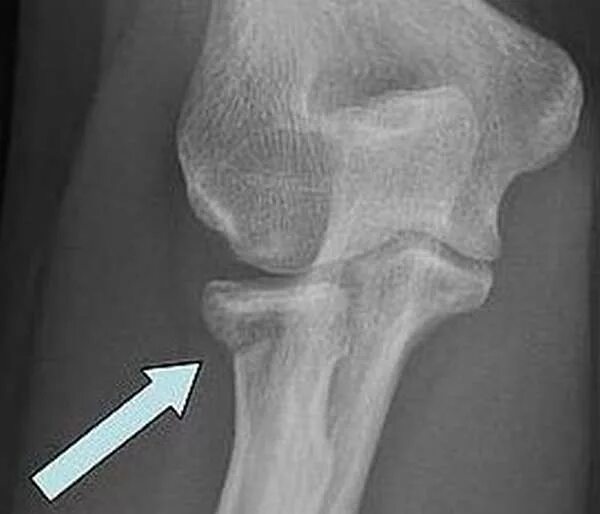

Мкб 10 закрытый перелом шейки